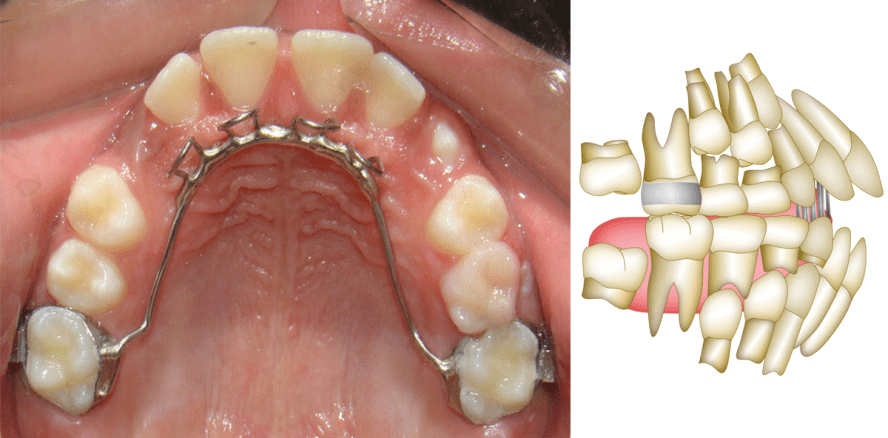

Die Behandlung im Milchzahn- und Wechselgebiss kann wie folgt zusammengefasst werden: Vor einem Alter von fünf Jahren sollten keine Apparaturen eingesetzt werden. Es wird lediglich eine Belohnungsstrategie empfohlen, d.h. vorzuschlagen, die Gewohnheit des Daumen- oder Schnullerlutschens gegen ein Spielzeug einzutauschen, das das Kind haben will.9 Ab einem Alter von fünf Jahren muss die Gewohnheit mithilfe einer Gaumenklammer oder Zungenspornen abgewöhnt werden.19 Wenn aufgrund einer Nasenblockade ein Mundatmungsproblem besteht, sollte das Kind zur Behandlung an einen Hals-Nasen-Ohren-Facharzt überwiesen werden. Nach Schließung des offenen Bisses sollte eine Sprach- oder Muskelfunktionsbehandlung eingeleitet werden, wenn die oralen Funktionsprobleme nach der Formungskorrektur nicht abklingen.23 Bei der Verwendung einer Gaumenklammer oder von Zungenspornen schließt sich der Biss, da die mechanischen Hindernisse, die der Daumen oder Schnuller und das falsche Zungenpressen bzw. die falsche Zungenstellung darstellten, beseitigt wurden und die Frontzähne wieder zu ihrer normalen vertikalen Entwicklung zurückfinden20 (Abb. 1a, b). Die klinische Stabilität der Behandlung beträgt nahezu 100 %6,11 und daher besteht kein Bedarf für eine zusätzliche Strategie zur Verbesserung. Die klinische Stabilität bezieht sich auf den Prozentsatz der Patienten, die langfristig einen positiven Überbiss haben.

3. Begleitende Verwendung einer Gaumenklammer oder von Zungenspornen während der Behandlung

Die Gaumenklammer beseitigt anhaltende schädliche orale Gewohnheiten sowie das Stoßen und die Positionierung der Zunge zwischen den Frontzähnen (Abb. 4).11,17 Dies verbessert die Effizienz der Behandlungsmechanik mit den Gummizügen, indem die Faktoren beseitigt werden, die das Schließen des Bisses verhindern. Die Zungensporne haben eine ähnliche Wirkung und konditionieren die Zunge dazu, eine weiter hinten gelegene Ruhestellung einzunehmen. Da anormalen Muskelfunktionen beim Wiederauftreten eines offenen Bisses als wichtige Faktoren angesehen werden, hilft die Verwendung dieser Apparaturen, die Muskelfunktion begleitend während der Behandlung zu korrigieren und somit zur Verbesserung der Stabilität der Behandlung eines offenen Bisses beizutragen.